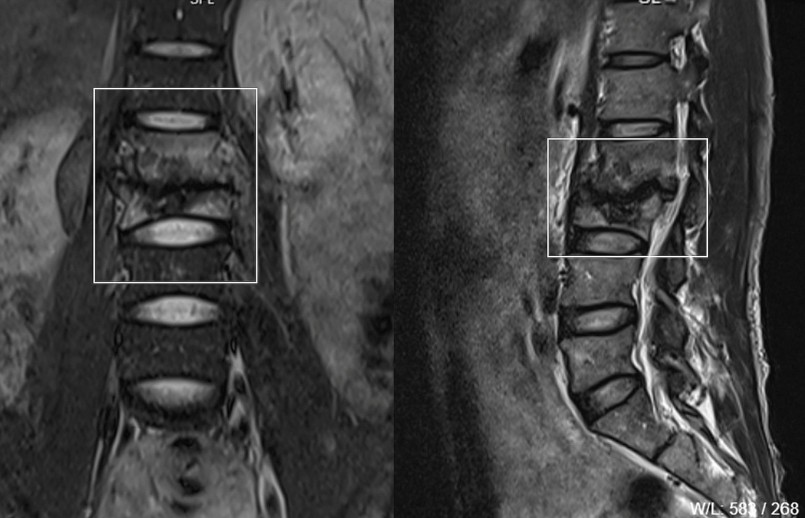

Kết quả chụp cộng hưởng từ (MRI) cho thấy thân đốt sống L2-L3 bị biến dạng, bờ khớp hẹp nham nhở và dính nhau, tín hiệu STIR tăng, phần mềm lân cận dày và phù nề, gây hẹp ống ngang mức nhưng chưa chèn ép chóp tủy. Đường kính trước sau của ống sống hẹp nhất còn 7mm. Ngoài ra, cơ thắt lưng chậu bên trái ngang mức L2-3 có ổ tụ dịch kích thước 30x18mm.

| Hình ảnh 2 đốt sống bị tổn thương tiêu huỷ - Ảnh: BVCC |

Sau khi hội chẩn trực tuyến với các chuyên gia chẩn đoán hình ảnh của Bệnh viện Hữu nghị Việt Đức, các bác sĩ tại Trung tâm Y tế Cẩm Khê (Phú Thọ) thống nhất chẩn đoán anh S. bị tiêu xương đốt sống L2-L3, chưa loại trừ khả năng lao cột sống.